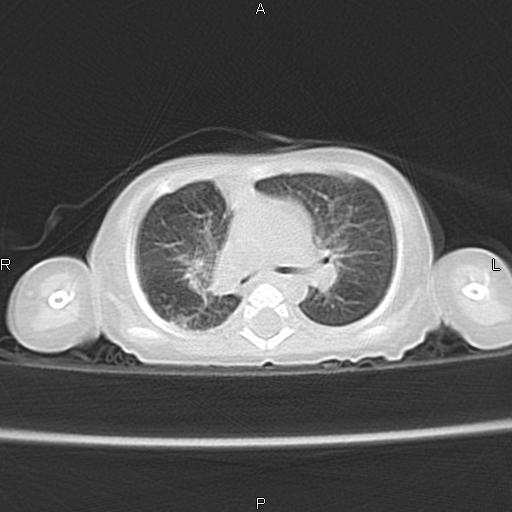

以下是引用aa13877358820在2010-7-26 12:35:00的发言:[br]男性,三个月,卧位胸片,咳嗽、气促、发热14天,两肺闻及细小水泡音。[br]